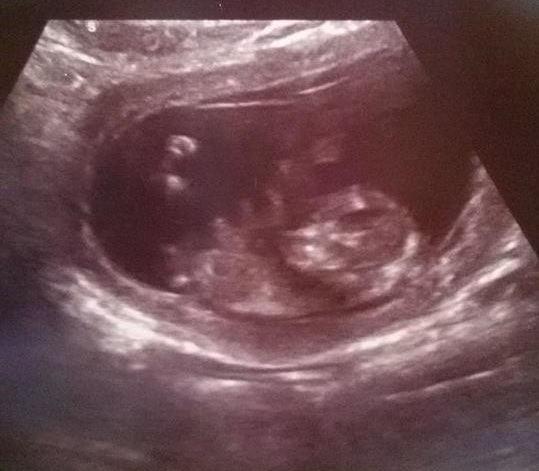

My sister-in-law has two ultrasound pictures about her baby. What do you think is the baby's gender?